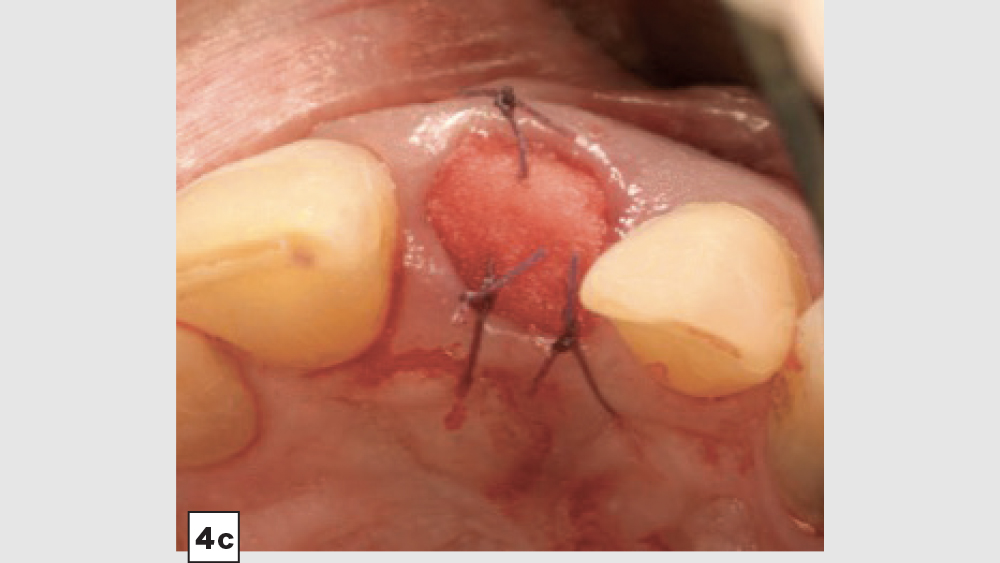

Four-Walled Socket Bone Grafting Technique (Figs. 4a–4d, 5a–5c)

1. Reflection: In most four-walled sockets, a partial mucoperiosteal flap should be reflected to allow for surgical access to the missing buccal plate. This will allow the clinician to place a membrane properly along the buccal plate.

4. Membrane: Because of the missing buccal plate, a longer-acting collagen cross-linked membrane (e.g., Newport Biologics Resorbable Collagen Membrane 3-4) or a PTFE (e.g., CytoSurg Non-Resorbable PTFE Membrane) should be used. The membrane should be trimmed in a modified V-shape (Fig. 5a).6 The narrower part of the membrane should encompass the entire missing buccal wall. Placement of the membrane should be within the confines of the socket, as extending the membrane over the external aspect of any remaining buccal wall will compromise the blood supply. The membrane should cover only the missing buccal wall; the other walls should not have membrane coverage, as this will decrease the healing of the socket. The goal of the membrane is to prevent the soft tissue from repopulating the defect. The wider part of the membrane should be trimmed so that it is slightly larger than the socket opening to allow for placement under the flap.

5. Closure: Closure should be completed with a 3-0 or 4-0 high-tensile suture material (e.g., PGA or PTFE) with a crisscross suture technique. Care should be exercised to avoid suturing through the membrane. Gut sutures (plain, chromic) should be avoided, as they have a compromised tensile strength and incision line breakdown may occur.